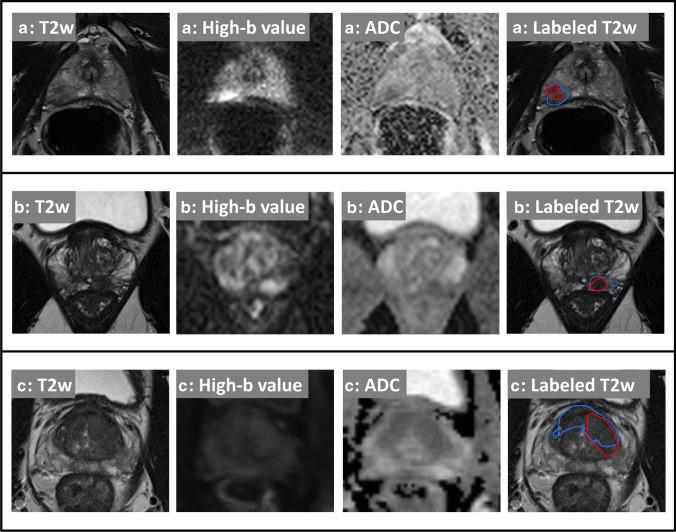

To evaluate a fully automatic deep learning system to detect and segment clinically significant prostate cancer (csPCa) on same-vendor prostate MRI from two different institutions not contributing to training of the system.

In this retrospective study, a previously bi-institutionally validated deep learning system (UNETM) was applied to bi-parametric prostate MRI data from one external institution (A), a PI-RADS distribution-matched internal cohort (B), and a csPCa stratified subset of single-institution external public challenge data (C). csPCa was defined as ISUP Grade Group ≥ 2 determined from combined targeted and extended systematic MRI/transrectal US-fusion biopsy. Performance of UNETM was evaluated by comparing ROC AUC and specificity at typical PI-RADS sensitivity levels. Lesion-level analysis between UNETM segmentations and radiologist-delineated segmentations was performed using Dice coefficient, free-response operating characteristic (FROC), and weighted alternative (waFROC). The influence of using different diffusion sequences was analyzed in cohort A.

In 250/250/140 exams in cohorts A/B/C, differences in ROC AUC were insignificant with 0.80 (95% CI: 0.74-0.85)/0.87 (95% CI: 0.83-0.92)/0.82 (95% CI: 0.75-0.89). At sensitivities of 95% and 90%, UNETM achieved specificity of 30%/50% in A, 44%/71% in B, and 43%/49% in C, respectively. Dice coefficient of UNETM and radiologist-delineated lesions was 0.36 in A and 0.49 in B. The waFROC AUC was 0.67 (95% CI: 0.60-0.83) in A and 0.7 (95% CI: 0.64-0.78) in B. UNETM performed marginally better on readout-segmented than on single-shot echo-planar-imaging.